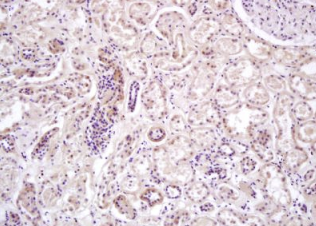

组织/细胞:人体肾组织;4%多聚甲醛固定石蜡包埋;

抗原提取:柠檬酸缓冲液(0.01M,pH 6),15min煮沸,用3%过氧化氢阻断内源性过氧化物酶30min;37℃下阻断缓冲液(正常山羊血清,C-00 05)20 min;

孵育:抗-prkaa2/ampkα2多克隆抗体,未结合1:200,在4°C下过夜,然后接合到二级抗体和DAB染色。